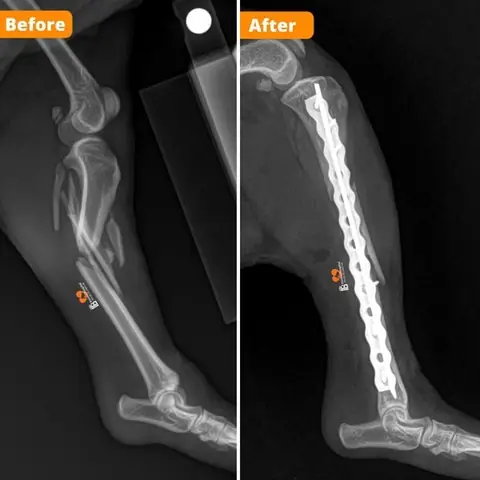

• Chụp X-quang (X-ray): Đây là phương pháp chẩn đoán hình ảnh chính yếu và bắt buộc để xác định chính xác vị trí, loại gãy xương (ví dụ: gãy kín, gãy hở, gãy xương vụn), mức độ nghiêm trọng và số lượng xương bị gãy. Đôi khi, có thể cần chụp nhiều góc độ khác nhau hoặc chụp chân đối diện để so sánh.

• Phẫu thuật chỉnh hình xương (Orthopedic Surgery): Đây là phương pháp điều trị phổ biến và hiệu quả nhất cho hầu hết các ca gãy xương nghiêm trọng. Phẫu thuật đòi hỏi trang thiết bị chuyên biệt và bác sĩ chuyên khoa Ngoại khoa/Chỉnh hình có kinh nghiệm.

• Cố định bên trong (Internal Fixation): Bác sĩ sẽ sử dụng các dụng cụ y tế như nẹp kim loại (bone plates), vít (screws), đinh (pins) hoặc dây (wires) để cố định các mảnh xương gãy lại với nhau từ bên trong cơ thể. Các dụng cụ này thường được để lại vĩnh viễn hoặc gỡ bỏ sau khi xương đã lành hoàn toàn.